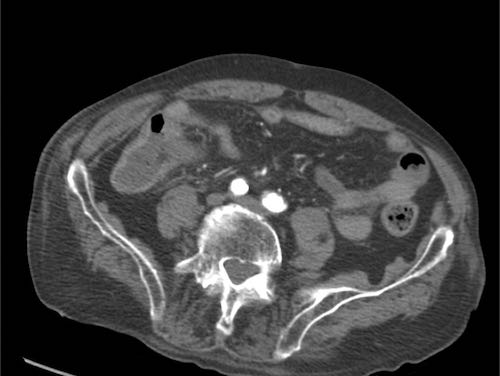

Bệnh nhân nam 79 tuổi, đang nằm viện hai ngày vì nhồi máu cơ tim, đột ngột xuất hiện đau hố chậu phải và CRP 70, nghi ngờ viêm ruột thừa.

Bệnh nhân đang được cách ly vì nghi ngờ nhiễm MRSA.

Siêu âm cho thấy ruột thừa bình thường kích thước 4 mm và dày thành hồi tràng đoạn cuối, xung quanh là mỡ viêm (*).

Cạnh hồi tràng quan sát thấy một bóng khí có thể có (mũi tên xanh).

Trong lòng hồi tràng, phát hiện một cấu trúc phản âm dạng tuyến tính (đầu mũi tên).

Hình ảnh trên nhiều mặt phẳng gợi ý đây là dị vật dẹt.

Ở một đầu, một cạnh sắc rõ ràng (mũi tên trắng) nhô ra vào mỡ viêm xung quanh (*).

CT axial xác nhận các phát hiện trên siêu âm và xác định một dị vật có hình dạng bất thường.